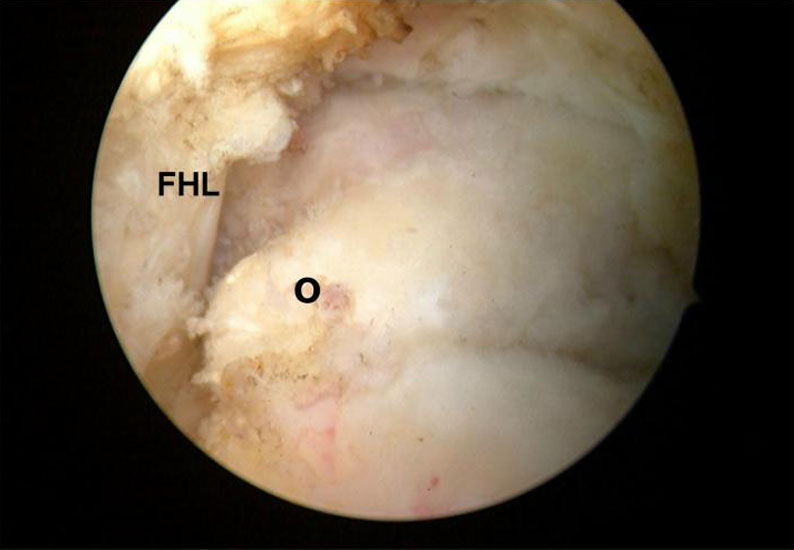

Abbildung Nr. 17 und 18, Video Nr. 3

Das arthroskopische Verfahren eignet sich auch zur Resektion multipler Ossikel (*) und Osteophyten (O). Hier ist der intraoperative Einsatz eines Bildverstärkers unabdingbar, um keine Knochenfragmente im Weichteilgewebe zu übersehen. Zur Osteophytenresektion können problemlos kleine Flachmeißel über die Arthroskopiezugänge verwendet werden (rechte Seite, m= medial, l= lateral, FHL=Flexor hallucis longus-Sehne).